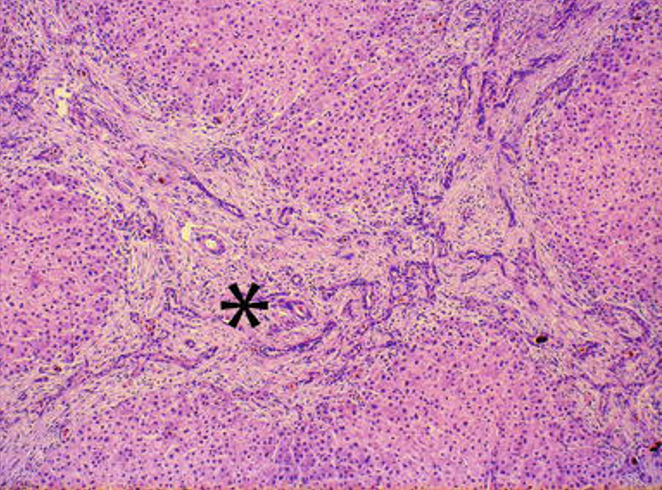

21

Q

A

portal fibrosis and bile duct hyperplasia

22

what caused this

biliary atresia